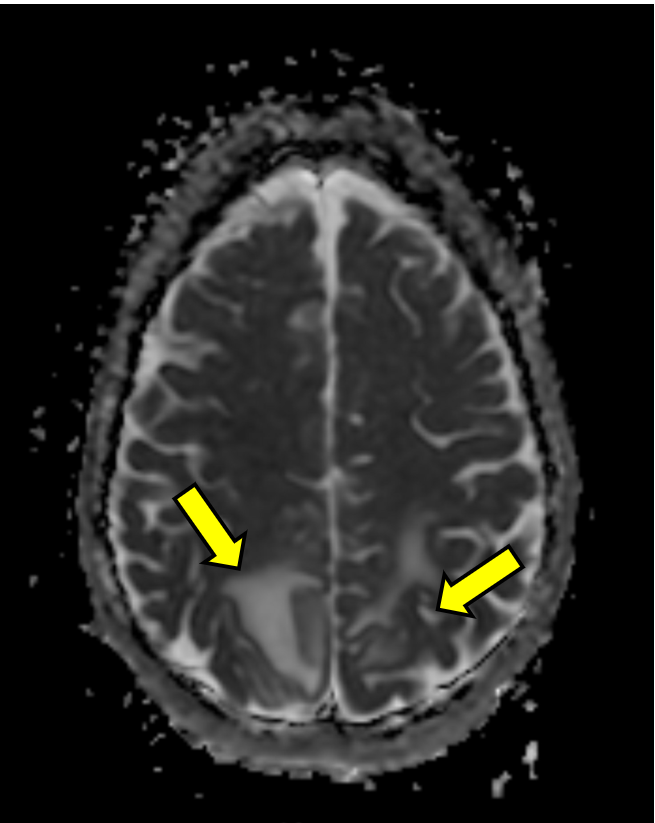

A few hours after admission she ultimately eloped during shift change. She returned to the same ED the next day after being found unresponsive outside again, was given Narcan en route as well as in the ED for bradypnea, and ultimately started on a naloxone drip, though she remained saturating well on room air. The initial temperature was 97.8°F and the initial BP was 121/83. Repeat head CT demonstrated the same vasogenic edema as seen previously (see Figure 1B). The patient was admitted again and remained normotensive. MRI with and without contrast demonstrated expansile T2/FLAIR hyperintense signal in the posterior frontal and parietal lobes, favored to be PRES (see Figure 1C and D).

Figure 1: Computed Tomography and Magnetic Resonance Imaging Demonstrating Posterior Reversible Encephalopathy Syndrome (PRES) Figure Caption: Initial (A) and next-day (B) CT imaging of concerning for PRES, with bilateral parietal vasogenic edema noted. MRI demonstrated expansile T2/FLAIR hyperintense signal in the posterior frontal and parietal lobes, favored to be PRES (C and D). Arrows correspond to areas of interest.

Initial (A) and next-day (B) CT imaging of concerning for PRES, with bilateral parietal vasogenic edema noted. MRI demonstrated expansile T2/FLAIR hyperintense signal in the posterior frontal and parietal lobes, favored to be PRES (C and D). Arrows correspond to areas of interest.